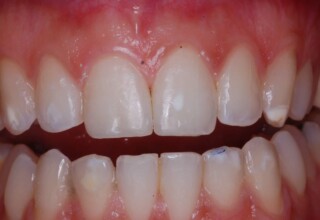

Όψεις Σύνθετης Ρητίνης

Οι όψεις ρητίνης προσφέρουν έναν οικονομικό τρόπο αισθητικής βελτίωσης της εμφάνισης των προσθίων δοντιών ενίοτε και των προγομφίων. Οι δυνατότητες τους πολλές, μπορούν να κάνουν και θαύματα! Ο μονός περιορισμός η κλινική ευχέρεια και η φαντασία του επεμβαίνοντος. Σε αυτήν την ασθενή οι τέσσερεις άνω τομείς είχαν ο καθένας το δικό του πρόβλημα(δυσχρωμία, απόκλιση) και επιπλέον: διαστήματα, πολλαπλές αποχρώσεις, κακή σχέση μεταξύ τους και με τα ούλα. Αποκαταστάθηκαν με τέσσερεις άμεσες όψεις ρητίνης (η μια πάνω σε στεφάνη πορσελάνης εμφυτεύματος!!!) οι οποίες κατασκευάστηκαν ενδοστοματικά!